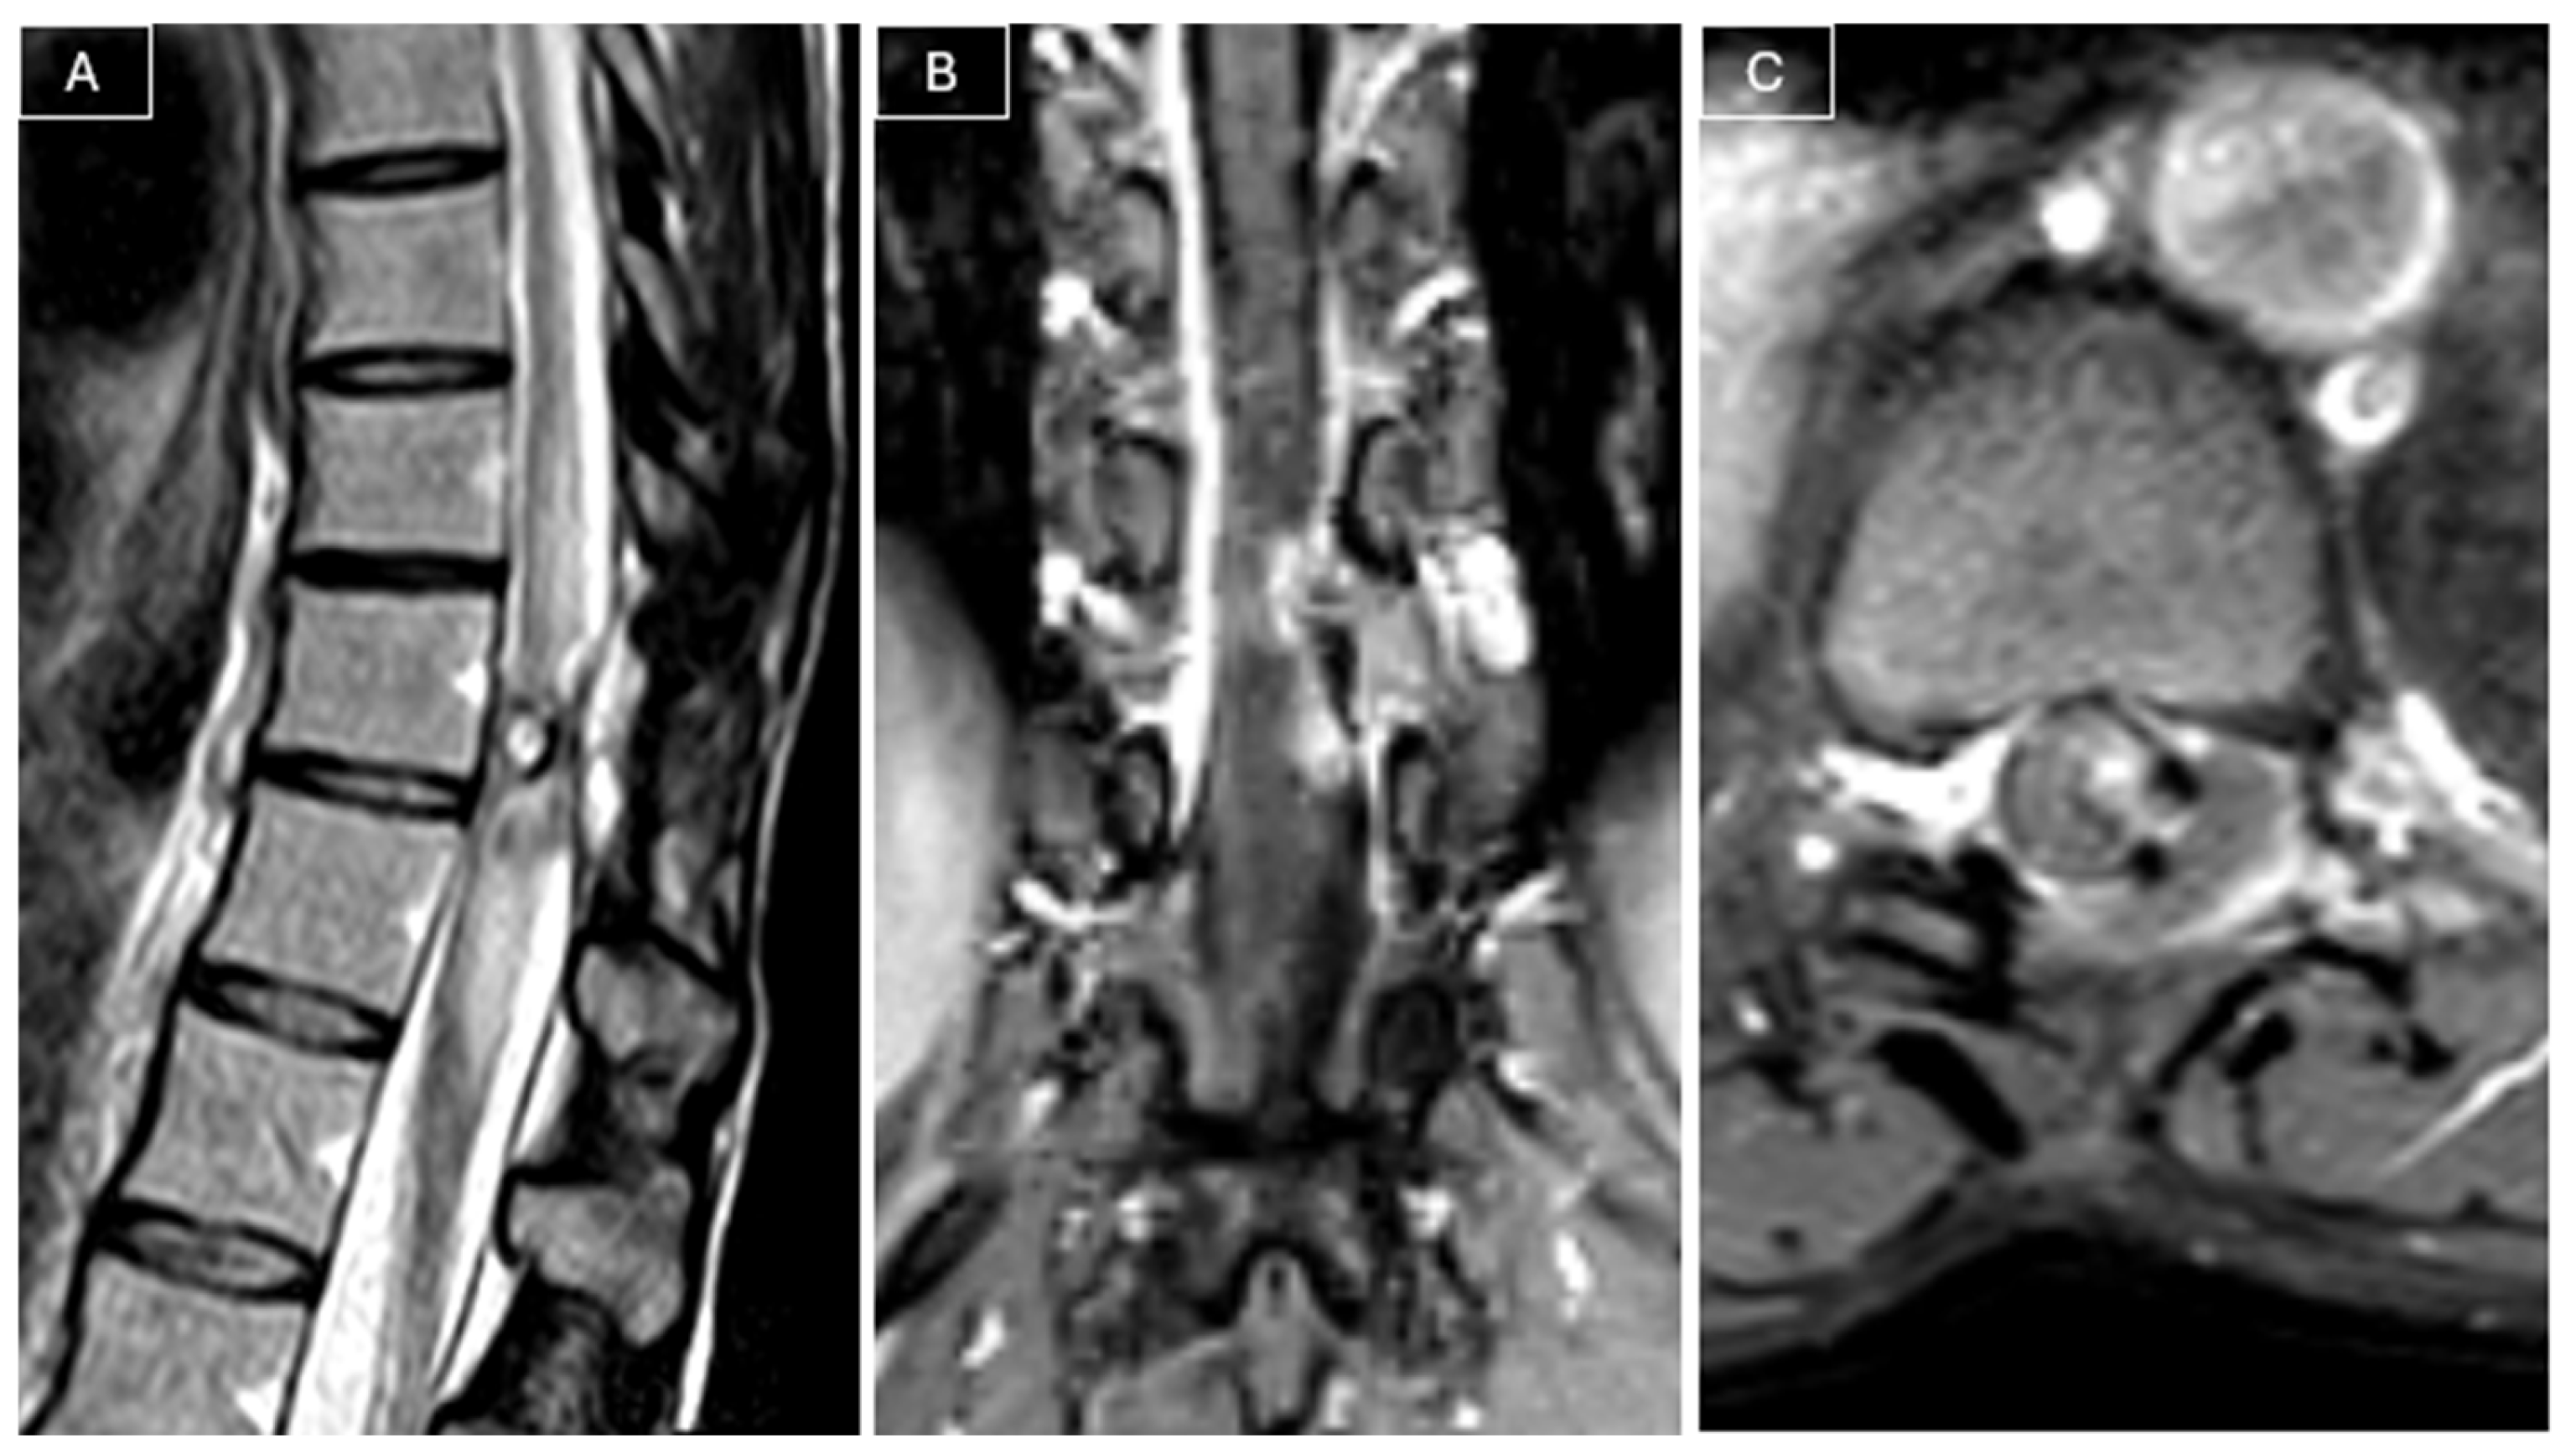

Radiological surveillance was performed at 2, 6, 12, and 18 months postoperatively with MRI. Follow-up MRI performed 18 months later revealed a recurrent lesion measuring 9 × 5 × 23 mm, in close contact with the spinal cord, associated with a T2 hyperintensity in the adjacent cord (see Figure 3).

Figure 3. MRI at 18-month follow-up revealed tumor recurrence. (A) Sagittal T2-weighted images showed a T2 hyperintensity in the adjacent cord. (B,C) Post-contrast T1-weighted images showed a nodular contrast-enhancing lesion in contact with the spinal cord, suspicious for tumor recurrence.